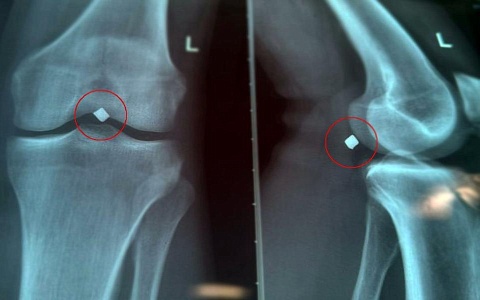

Женщина с металлоконструкцией в позвоночнике родила здорового ребенка